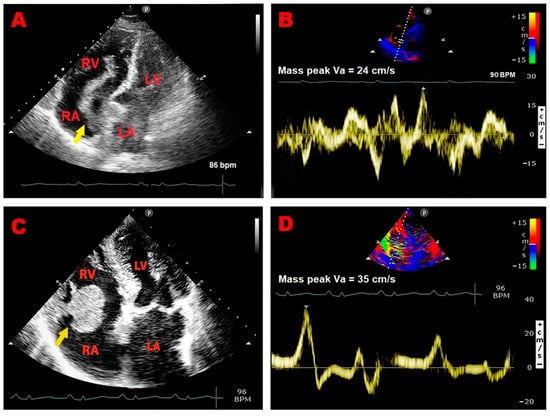

Representative examples of RA thrombus, myxoma, and vegetation assessed by TTE implemented with PW-TDI are illustrated in Figure 3A–F.

Figure 3.

Representative examples of RA thrombus, myxoma, and vegetation assessed by TTE implemented with PW-TDI. (A) Transthoracic echocardiography. Apical four-chamber view, showing large S-shaped RA thrombus (yellow arrow) entrapped in the Chiari network, prolapsing through the tricuspid valve into the right ventricle. (B) PW-TDI assessment of the thrombotic mass motility: the pattern of incoherent motion is typical of a pathological RA mass. (C) Transthoracic echocardiography. Apical four-chamber view, revealing RA atrial multilobulated, hypermobile, echogenic cauliflower mass attached to the tricuspid lateral annulus with a short stalk (yellow arrow), compatible with a pedunculated myxoma. (D) PW-TDI assessment of the RA myxoma motility: the mass motility is totally independent of the cardiac cycle. (E) Transthoracic echocardiography. Apical four-chamber view, demonstrating an echogenic mass attached to the fossa ovalis, extending into the RA (yellow arrow), compatible with RA myxoma. (F) Pattern of uncoordinated motion of RA myxoma assessed by PW-TDI. (G) Transthoracic echocardiography. Apical four-chamber view, highlighting large vegetation attached to the pacemaker lead in the right atrium (yellow arrow) of a patient with infective endocarditis. (H) Pattern of incoherent motion of RA vegetation on PW-TDI. LA, left atrium; LV, left ventricle; PW, pulsed wave; RA, right atrium; RV, right ventricle; TTE, transthoracic echocardiography; TDI, tissue Doppler imaging; Va, antegrade velocity. (C,D) are reproduced from the paper [24] (license number 5917070978039).